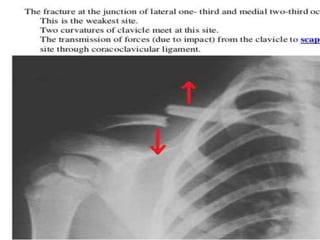

Supracodylar fracture – common and most serious fractures in

childhood

Mechanism- Fracture is caused by a fall on an out-stretched hand.

As the hand strikes the ground, the elbow is forced into

hyperextension resulting in fracture of the humerus above the

condyles.